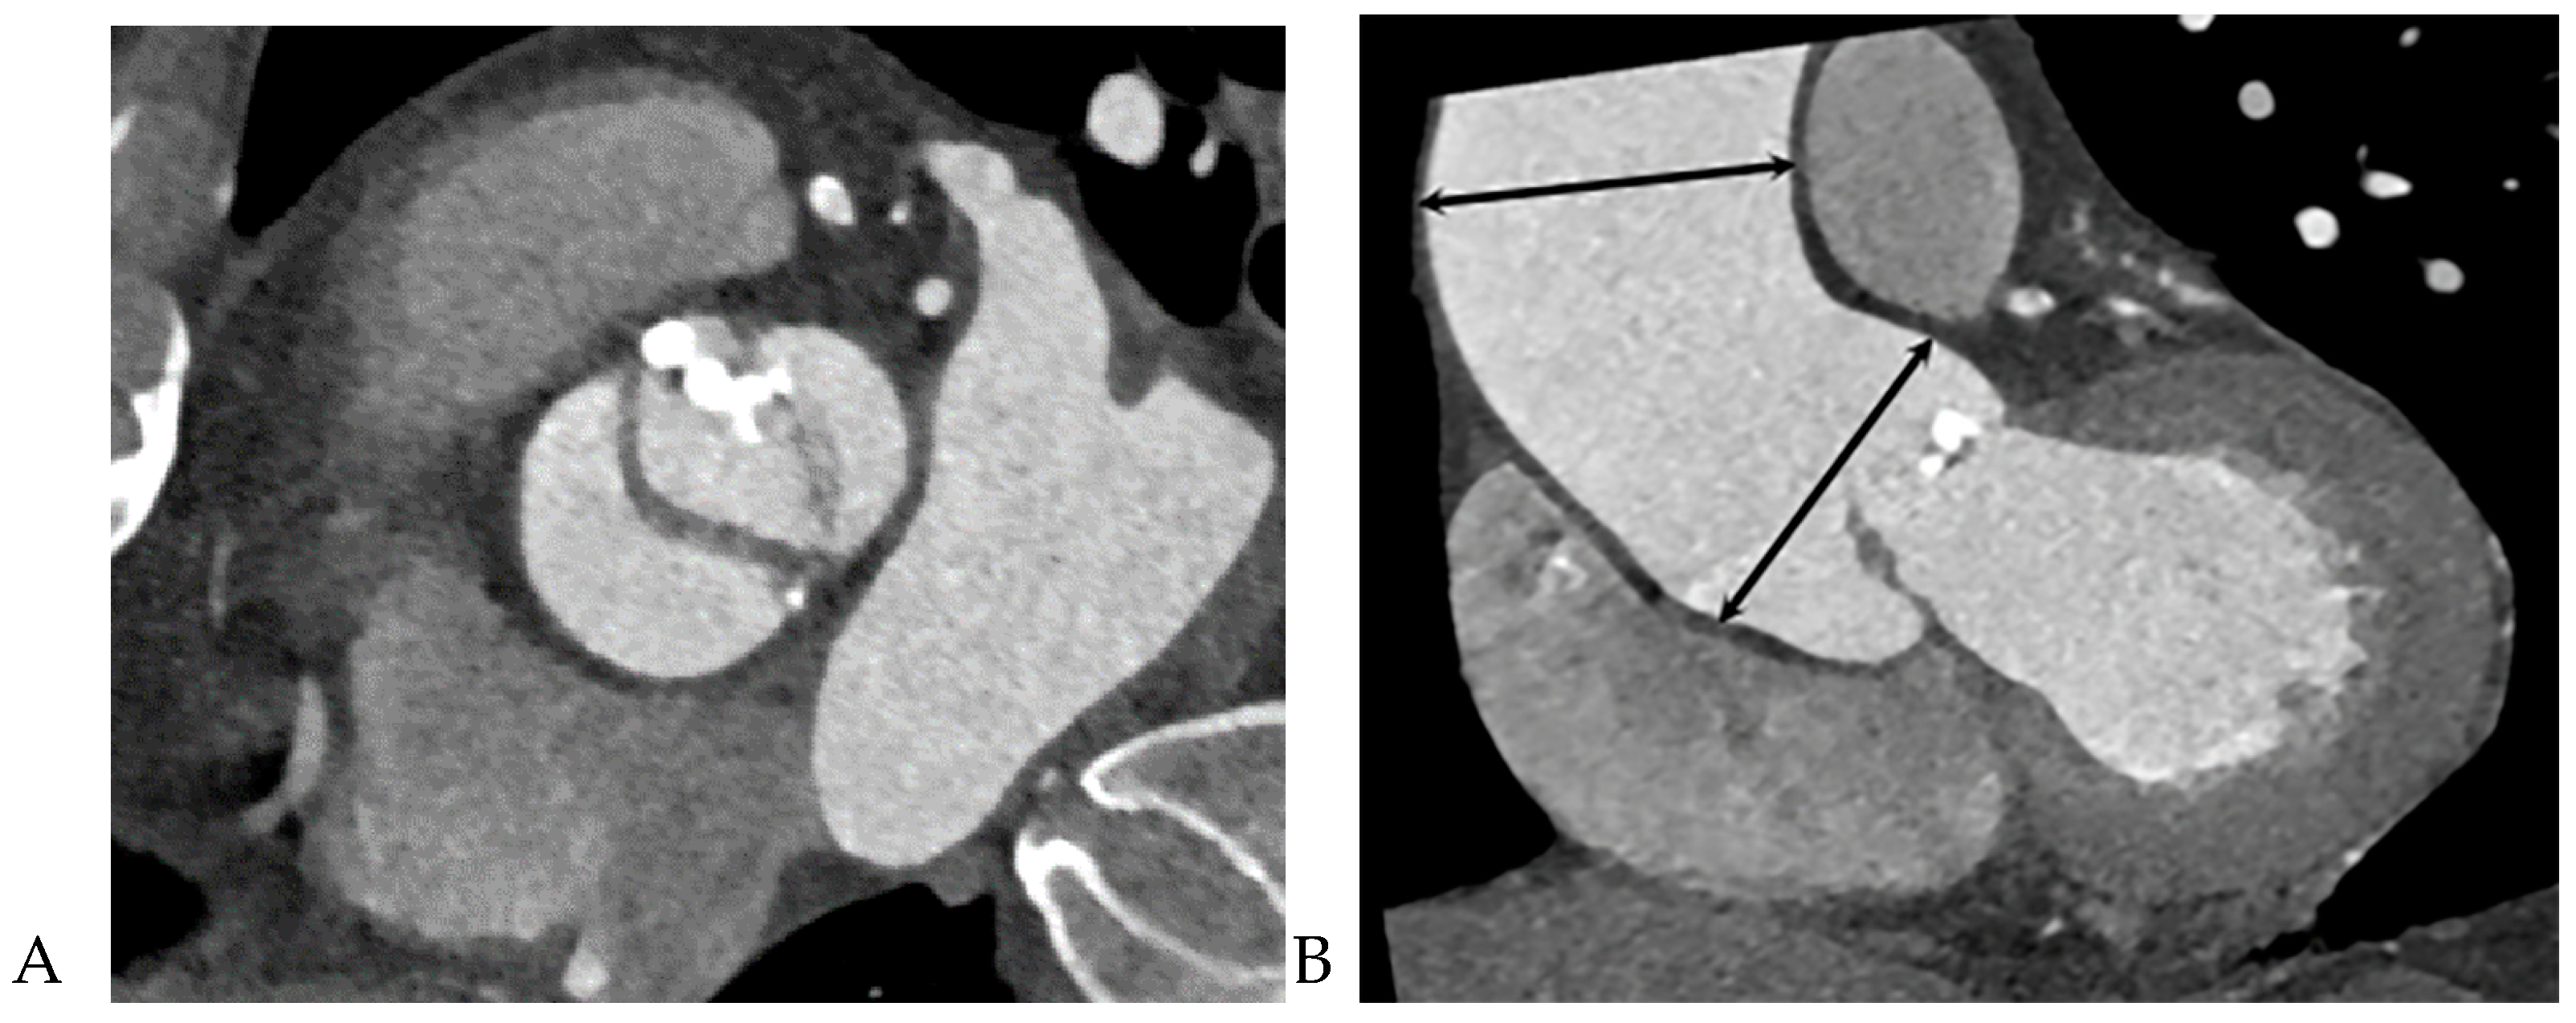

3. Results

Figure 4. Bicuspid aortic valve (BAV) with raphe with ascending aorta root dilatation in a 48-year-old male. (A) Double oblique CT reconstruction parallel to the aortic valve during systole demonstrates a BAV with fusion of the right and left coronary cusps. (B) Double-oblique coronal CT reconstruction through the left ventricular outflow tract during systole shows diameters of sinuses of Valsalva 40.8 mm (size index 2.02 cm/m2) mm and mid ascending aorta 53.6 mm (size index 2.65 cm/m2), which were measured at mid-systole. (C) Color Doppler echocardiogram shows a jet regurgitating into the left ventricle. Aortic regurgitation was considered mild.

Figure 5. Bicuspid aortic valve (BAV) without raphe and combined aortic root as well as mid ascending aorta in a 64-year-old male. (A) Double oblique CT reconstruction parallel to the aortic valve demonstrates thickened, calcified BAV cusps without raphe. (B) Diameters of the sinuses of Valsalva 43.5 mm (size index 2.24 cm/m2) and mid ascending aorta 46.4 mm (size index 2.48 cm/m2), which were measured at mid-systole. (C) Continuous-wave Doppler recording of the aortic stenosis jet from an apical approach shows a maximum velocity of 3.07 m/sec. The continuity equation of the aortic valve area was 1.2 cm2, corresponding to moderate aortic stenosis.